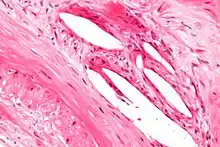

The internal elastic lamina or internal elastic lamella is a layer of elastic tissue that forms the outermost part of the tunica intima of blood vessels. It separates tunica intima from tunica media.

It is readily visualized with light microscopy in sections of muscular arteries, where it is thick and prominent, and arterioles, where it is slightly less prominent and often incomplete.[1] It is very thin in veins and venules.[1] In elastic arteries such as the aorta, which have very regular elastic laminae between layers of smooth muscle cells in their tunica media, the internal elastic lamina is approximately the same thickness as the other elastic laminae that are normally present.[2]

There is small amount of subendothelial connective tissue between basement membrane of endothelial cells and internal elastic lamina.[3]

Reduplication of internal elastic lamina can be seen in elderly individuals due to intimal fibroplasia, which is part of the aging process.[4]